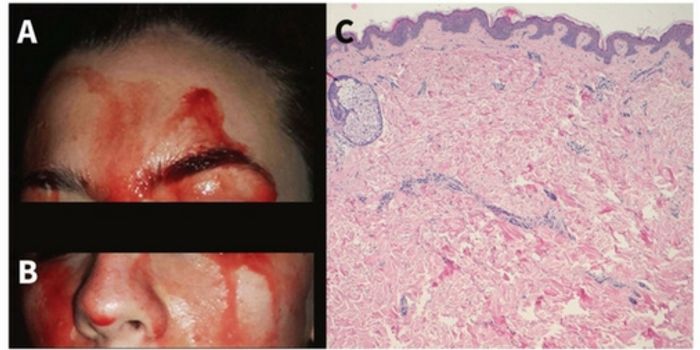

OCT 24, 2017Clinical & Molecular DXDoctors have confirmed that a 21-year-old Italian woman does, indeed, sweat blood. Not much is known about this ultra ra ...